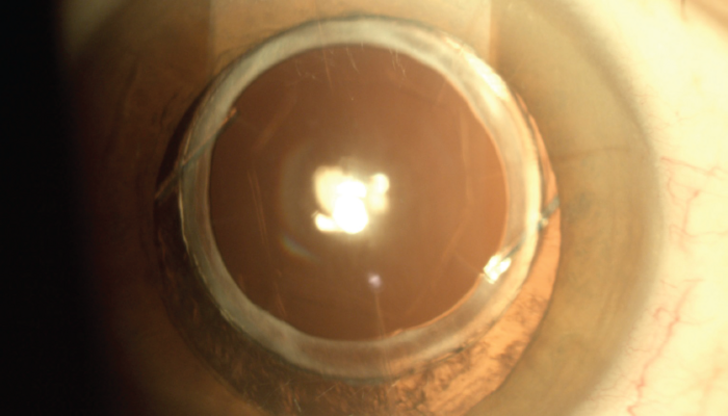

Premium lens cataract surgeries have transformed vision correction for millions globally, yet complications such as glare, halos, and blurry vision can leave some patients disappointed. Dr. Arun C. Gulani, a world-renowned eye surgeon, offers a groundbreaking, non-invasive approach to addressing these challenges by optimizing the cornea to work in harmony with the implanted lens. Learn how this innovative solution restores vision and exceeds patient expectations, all without going back under the knife.

Dr. Gulani’s method focuses on corneal optimization rather than invasive lens replacement, providing a non-surgical, effective solution for post-surgery vision complications.

Premium lens implants are just one ingredient in the overall “vision recipe.” By precisely reshaping the cornea to align with the lens, Dr. Gulani restores clarity while maintaining the integrity of the original surgery.